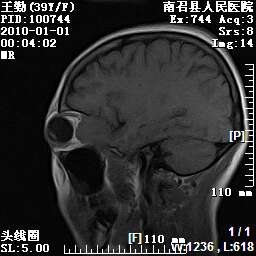

以下是引用随光逐影在2010-1-22 9:03:00的发言:[br]考虑左侧中颅窝(蝶骨翼区)脑膜瘤侵犯蝶骨翼并突入左侧眼眶。

以下是引用水过无痕在2010-1-22 14:55:00的发言:[br]一、定位:颅外占位;二、定性:恶性可能性大;三、组织来源:来源于左侧眼外直肌或其他部位;考虑为:横纹肌肉瘤>转移瘤>脑膜瘤.